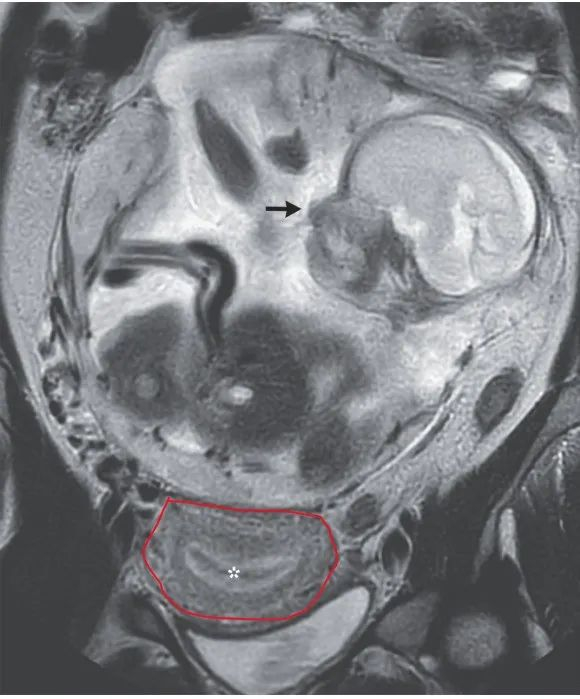

“在腹腔妊娠情况下,母亲的死亡率约为5%,胎儿存活率仅为1‰。若通过手术终止妊娠,可能存在大出血及骨盆、泌尿道损伤,需要血管外科、创伤外科、泌尿科等多学科协作。”美国德州农工大学医疗中心报告指出。

美国德州农工大学医疗中心报告一例矢状腹腔妊娠,胎儿脊柱可见。图源/Proc(Bayl Univ Med Cent)